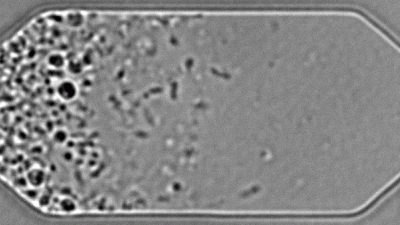

محطات 30 مارس 2021 سابقة طبية: خلية اصطناعية تنمو وتنقسم مثل الطبيعية في سابقة طبية جديدة للهندسة الوراثية، طور علماء من معهد ماساتشوستس الأمريكي للتكنولوجيا خلية اصطناعية تسمى «JCVI-syn3A» تنمو وتنقسم مثل الخلية